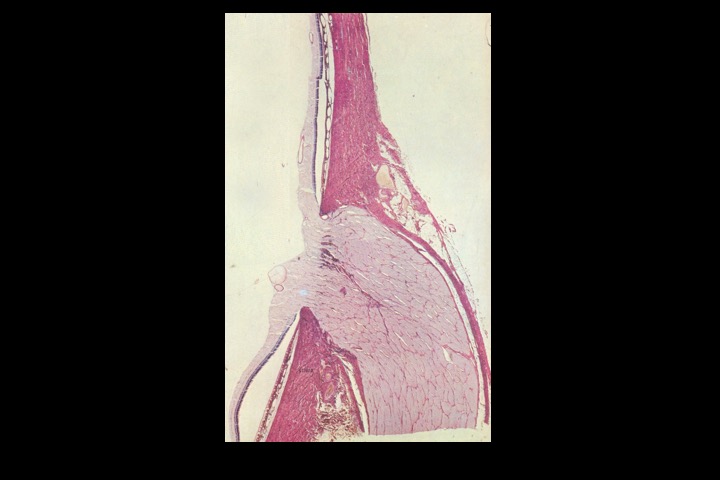

Disco do nervo óptico_1